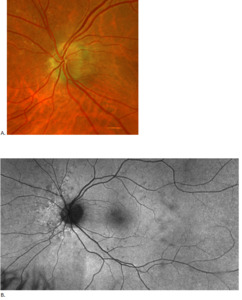

Posterior segment revealed IOL implants that were clear and centered after YAG Capsulotomy in both eyes. The optic nerve heads were both crowded with cupping of 0.10/0.10 (H/V) OU. The neuroretinal rim was intact in the right eye with no evidence of hemes, pallor, edema, or neovascularization of the disc. When observing the left eye, an inferior and inferior temporal rim hemorrhage was noted. Clinically, there was no apparent edema. There was a questionable area of swelling inferior temporal and superior temporal, but it was difficult to view. The vessels surrounding the optic nerve did not appear to be obscured and no spontaneous venous pulse was noted. The macular area was flat with even pigment and no clinically significant macular edema was present in either eye. Vessels displayed a normal AV ratio. The peripheral exam noted no holes, breaks, or tears in either eye. Finally, giant cell arteritis (GCA) symptoms of were ruled out.

On this visit, the patient’s posterior pole revealed a blurred inferior temporal neuroretinal rim in both the left and right eyes. The right eye previously had no appearance of edema in the initial visit. The discs were crowded at .10/.10 OU as noted at initial visits and no hemorrhages were seen on this examination. All other structures posteriorly were consistent with the original examination.

After additional testing was completed, and comparison of previous photos were conducted, it was determined that the patient had not only optic disc drusen, but also possible bilateral amiodarone optic neuropathy. The photos 4 months apart shows increasing pallor in the left eye and a blood vessel at 7 o’clock that did not look obscured initially but was evidently more pronounced on the follow up when comparing the initial and follow-up photos. This shows the importance of quality serial fundus photography.

Right image is original exam with inferior hemorrhage. Left image is 4-month follow-up visit. Resolution of the hemorrhage is seen, but atrophy of the disc overall should be noted. Vessel at 7 o’clock should also be noted. It appears much more pronounced than on initial visit.